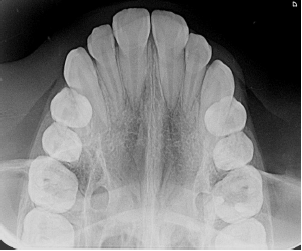

Qual a técnica radiográfica apresentada na imagem?